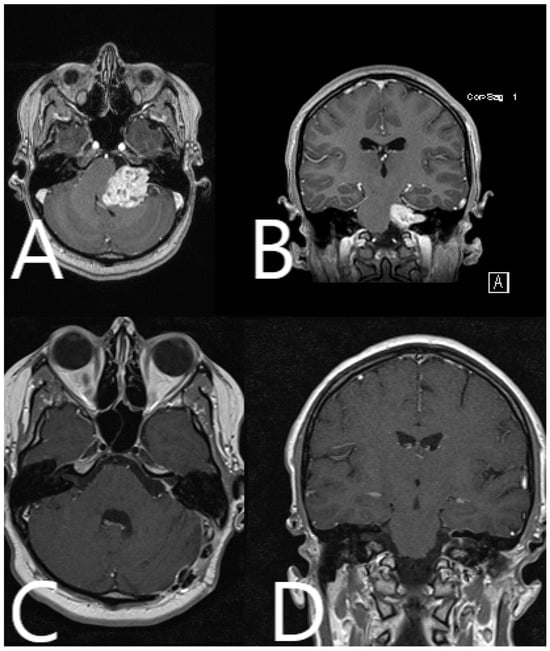

| Patient Number | Segmented Structures in AR Advantages: Craniotomy Planning, Dural Opening, Relations of Tumor to CN V, Localization of Origin of CVI and CVIII at the Brain Stem, Relations of Tumor to Brain Stem, Localization of IV Ventricle, Segmentation of Tumor Cyst, Localization of Structures of the Middle Ear for Facilitation of Drilling on Inner Acoustic Meatus, Relations of Tumor to Arterial Vessels and to Petrosal Vein | ||||||||||

|---|---|---|---|---|---|---|---|---|---|---|---|

| Sigmoid Sinus | Transverse Sinus | Tumor Outline | CN VII and VII Origin at Brain Stem | CN V | Petrous Vein | Arterial Vessels (AICA, PICA, SCA) | Brain Stem | Middle Ear, Cochlea and Semicircular Canals | Pyramidal Tract | IV Ventricle | |